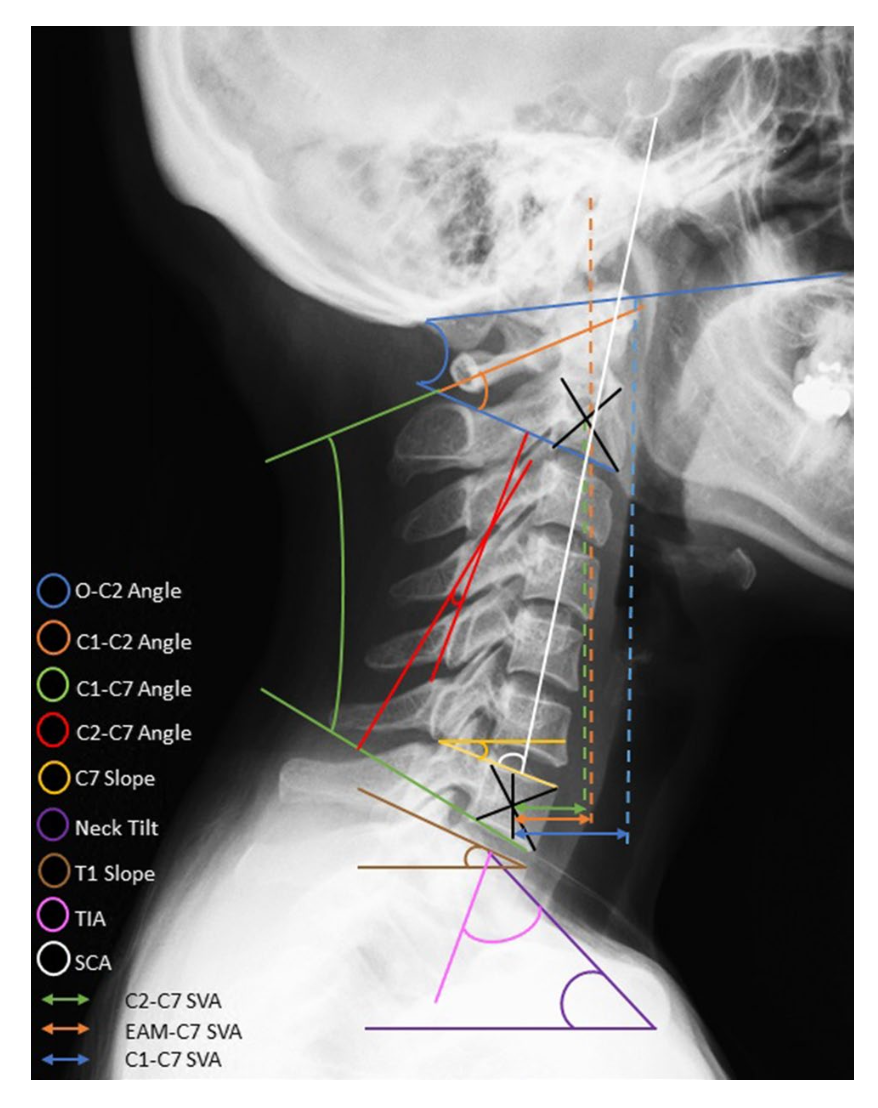

많은 연구자들은 목의 정상적인 각도를 통계화, 수치화, 일반화하기는 어렵기 때문에 다양한 방법을 통해 그 각 개인에게 맞는 적절한 기준을 설정하고 판단해야 한다고 말합니다. 그리고 X-ray 촬영을 통해 제시한 그 적절한 방법은 다음과 같습니다.

→ Pelvic incidence

→ Lumbar lordosis

→ Thoracic lordosis

→ T1 slope

→ Thoracic inlet angle

→ Cervical lordosis

→ SVA

→ CBVA

→ Cervical tilt

→ Neck tilt

→ Cranial tilt

Jouibari MF, Le Huec JC, Ranjbar Hameghavandi MH, Moghadam N, Farahbakhsh F, Khadivi M, Rostami M, K

병원에서, 센터에서 말하는 ‘거북목’, ‘일자목’이라는 기준에서 벗어난 비정상 판정을 받기 위해서 필요한 X-ray 평가에서 사용되어야 하는 방법(parameter, 한도)은 11개에 이릅니다. 여러분은 이런 평가를 통한 진단을 받은 기억이 있나요?